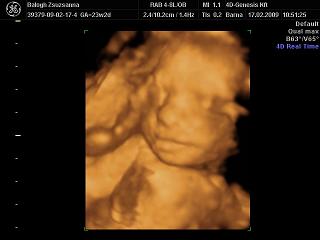

4D: előtte 3az egyben kávé+kóla+csoki. Muszáj volt, mert Adél drága csak délután kezd el mocorogni általában… De bevált, izgett- mozgott a drága!

Jajj

Magdi, nagyon be fog nektek is jönni, már olyan szépen látszik a kis arca, a vonásai!

Tiszta apja a kiscsaj, párom jól el is érzékenyült hogy ennyire hasonlít rá!

És jópár mosolygós kép készült róla: párom akkor simizte a hasam...

Adél